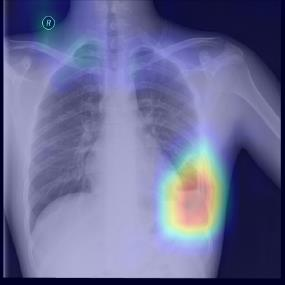

Chest X-ray (CXR) is the most typical diagnostic X-ray examination for screening various thoracic diseases. Automatically localizing lesions from CXR is promising for alleviating radiologists' reading burden. However, CXR datasets are often with massive image-level annotations and scarce lesion-level annotations, and more often, without annotations. Thus far, unifying different supervision granularities to develop thoracic disease detection algorithms has not been comprehensively addressed. In this paper, we present OXnet, the first deep omni-supervised thoracic disease detection network to our best knowledge that uses as much available supervision as possible for CXR diagnosis. We first introduce supervised learning via a one-stage detection model. Then, we inject a global classification head to the detection model and propose dual attention alignment to guide the global gradient to the local detection branch, which enables learning lesion detection from image-level annotations. We also impose intra-class compactness and inter-class separability with global prototype alignment to further enhance the global information learning. Moreover, we leverage a soft focal loss to distill the soft pseudo-labels of unlabeled data generated by a teacher model. Extensive experiments on a large-scale chest X-ray dataset show the proposed OXnet outperforms competitive methods with significant margins. Further, we investigate omni-supervision under various annotation granularities and corroborate OXnet is a promising choice to mitigate the plight of annotation shortage for medical image diagnosis.